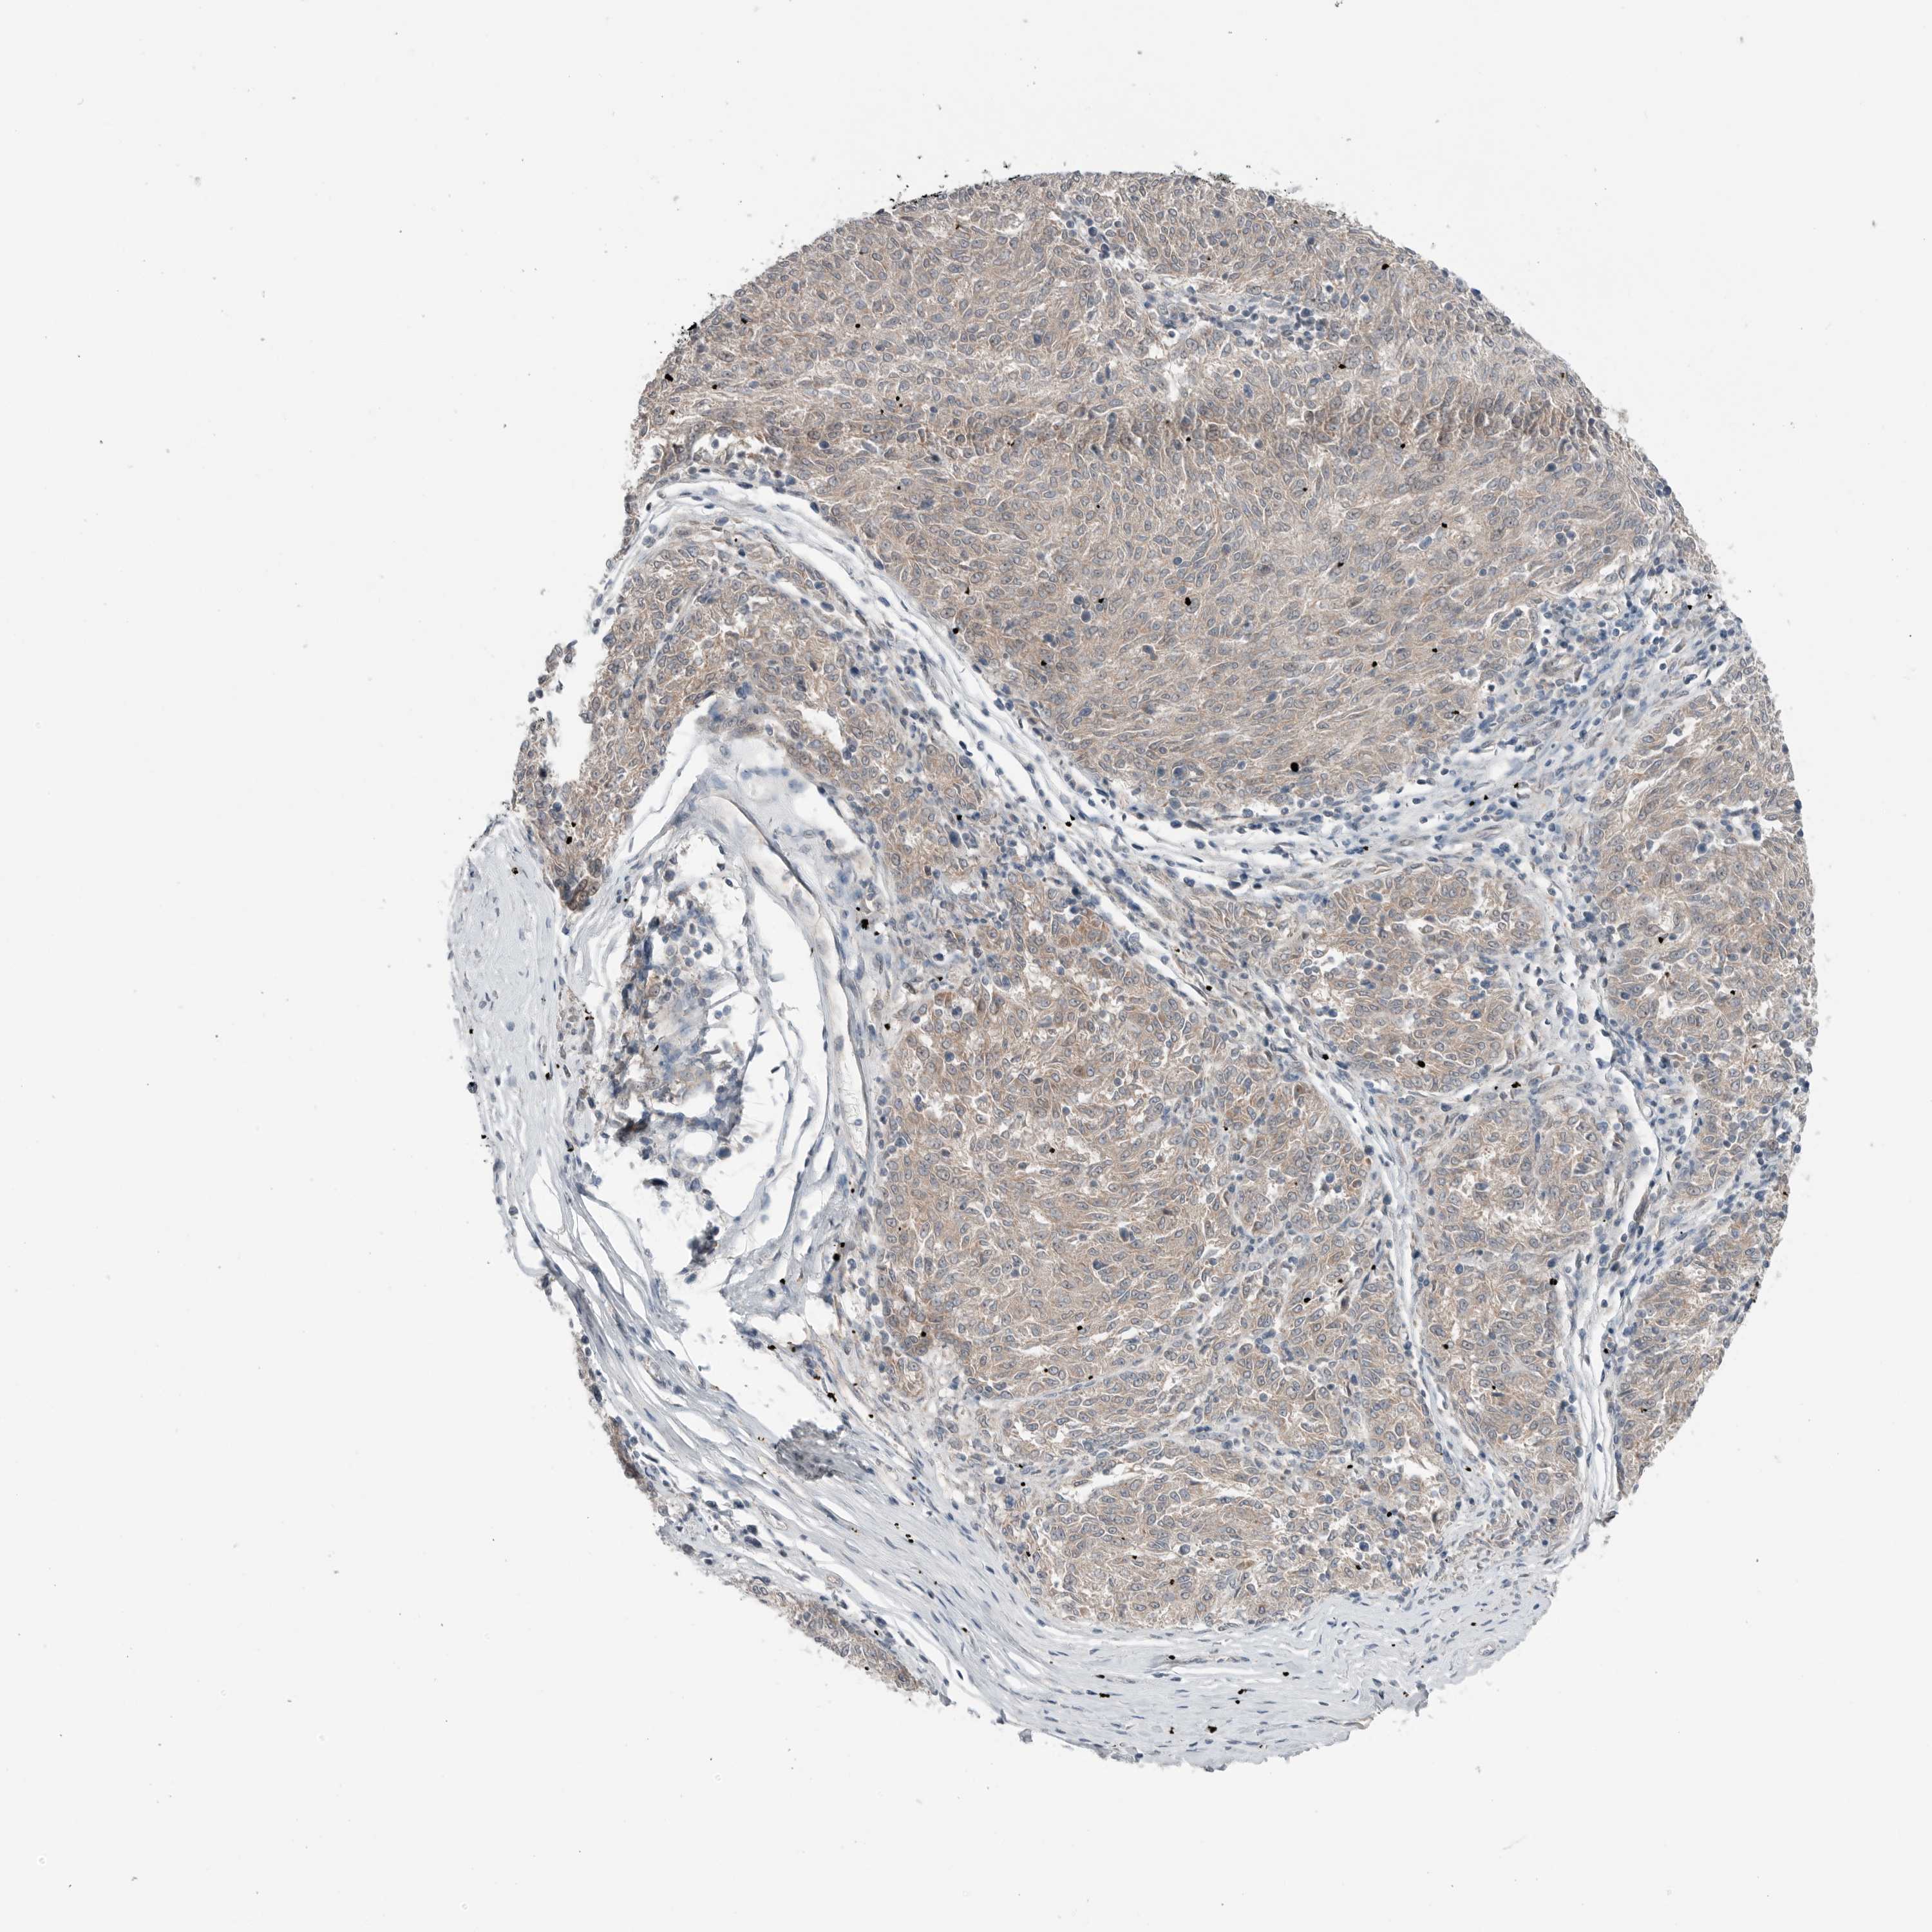

MELANOMA - Protein expressioni

A mouse-over function shows sample information and annotation data. Click on an image to view it in a full screen mode. Samples can be filtered based on level of antibody staining by selecting one or several of the following categories: high, medium, low and not detected. The assay and annotation is described here.

Note that samples used for immunohistochemistry by the Human Protein Atlas do not correspond to samples in the TCGA dataset.

Antibody stainingi

Antibody staining in the annotated cell types in the current human tissue is reported as not detected, low, medium, or high, based on conventional immunohistochemistry profiling in selected tissues. This score is based on the combination of the staining intensity and fraction of stained cells.

Each image is clickable and will lead to virtual microscopy that enables deeper exploration of all samples and also displays staining intensity scores, fraction scores and subcellular localization as well as patient and tissue information for each sample.

Antibody HPA024823

Staining

High

Medium

Low

Not detected

Intensity

Strong

Moderate

Weak

Negative

Quantity

>75%

75%-25%

<25%

None

Location

Nuclear

Cytoplasmic/membranous

Cytoplasmic/membranous,nuclear

Malignant melanoma, NOS

Malignant melanoma, Metastatic site